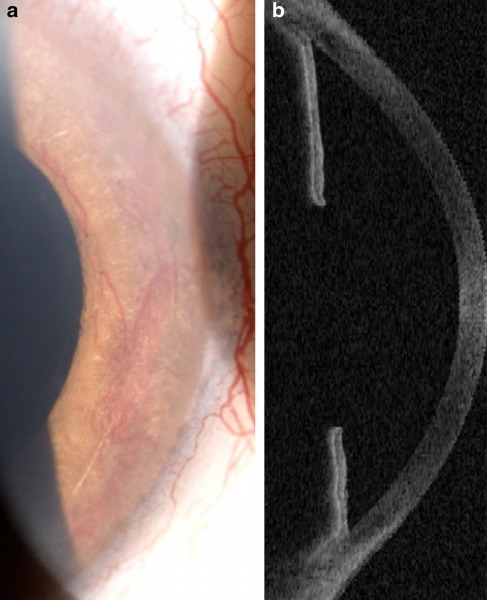

检查显示,患者右眼最佳矫正视力(BCVA)为 2/20,左眼失明。眼前节检查显示双眼虹膜新生血管(图 1a),光学相干断层扫描(OCT)显示房角关闭(图 1b)。30-2 Humphrey 视野测试显示一个大的弧形暗点。眼底检查显示缺血性视网膜病变,双眼视盘区新生血管(图 2),右眼视网膜前膜覆盖黄斑区,周边视网膜缺血。

图 1a 为眼前节检查显示双眼虹膜发红,图 1b 为 OCT 显示房角关闭